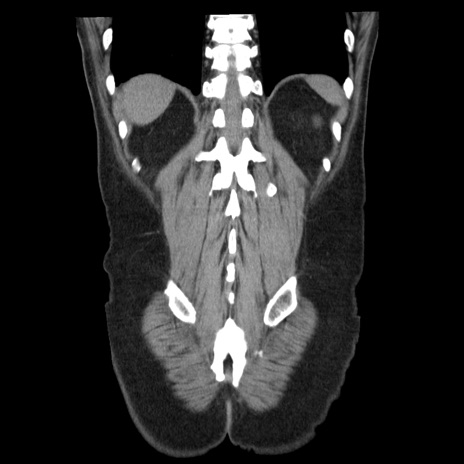

症例29(冠状断像)

【症例】40歳代男性

【現病歴】2日前から胃痛あり。徐々に周期的な激痛に変化した。本日になっても激痛があるため受診。

【身体所見】意識清明、BT 38-39℃台あり、腹部:膨満、やや硬、右下腹部に圧痛あり。

【データ】WBC 8500、CRP 23.26